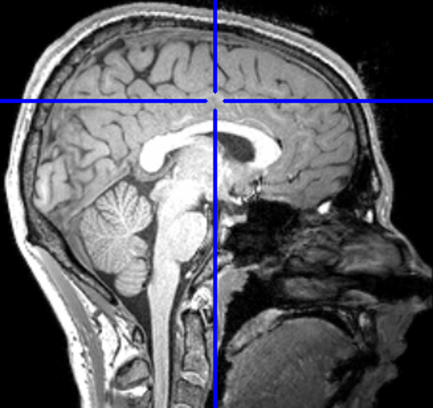

Computer Science + Neuroscience

The Human Brain is a Nonlinear Computational System

- Using Symbolic Regression to find Nonlinear Models of Functional and Effective Connectivity within fMRI data

- Discovering Generative Functions Describing Anatomical Connectivity

- Generating synthetic fMRI data

- Aligning fMRI data based on functional space